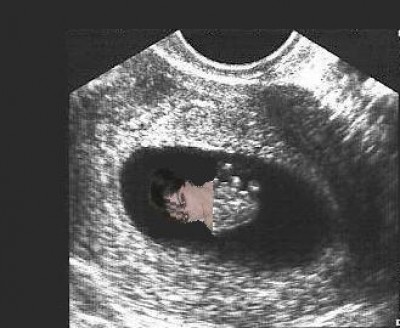

We had a little scare on Friday and I was given an early ultrasound. Fortunately, everything looked good. Baby measured just right for it's age (about 8wks) at 1.5cm and the little heart was beating along at a steady 145bpm (also very good). Everything else looked good as well. I thought I would include a picture for anyone interested.

baby2.jpg

baby2.jpg [ 19.12 KiB | Viewed 4707 times ]